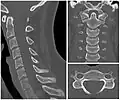

X-ray of cervical vertebrae

X-ray of cervical spine in flexion and extension